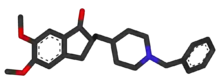

Medications used to treat the cognitive symptons of Alzheimer's disease rather than the underlying cause include: four acetylcholinesterase inhibitors (tacrine, rivastigmine, galantamine, and donepezil) and memantine, an NMDA receptor antagonist. The acetylcholinesterase inhibitors are intended for those with mild to severe Alzheimer's, whereas memantine is intended for those with moderate or severe Alzheimer's disease.[119] The benefit from their use is small.[172][173][174][13]

Reduction in the activity of the cholinergic neurons is a well-known feature of Alzheimer's disease.[175] Acetylcholinesterase inhibitors are employed to reduce the rate at which acetylcholine (ACh) is broken down, thereby increasing the concentration of ACh in the brain and combating the loss of ACh caused by the death of cholinergic neurons.[176] There is evidence for the efficacy of these medications in mild to moderate Alzheimer's disease,[177][172] and some evidence for their use in the advanced stage.[172] The use of these drugs in mild cognitive impairment has not shown any effect in a delay of the onset of Alzheimer's disease.[178] The most common side effects are nausea and vomiting, both of which are linked to cholinergic excess. These side effects arise in approximately 10–20% of users, are mild to moderate in severity, and can be managed by slowly adjusting medication doses.[179] Less common secondary effects include muscle cramps, decreased heart rate (bradycardia), decreased appetite and weight, and increased gastric acid production.[177]

Glutamate is an excitatory neurotransmitter of the nervous system, although excessive amounts in the brain can lead to cell death through a process called excitotoxicity which consists of the overstimulation of glutamate receptors. Excitotoxicity occurs not only in Alzheimer's disease, but also in other neurological diseases such as Parkinson's disease and multiple sclerosis.[180] Memantine is a noncompetitive NMDA receptor antagonist first used as an anti-influenza agent. It acts on the glutamatergic system by blocking NMDA receptors and inhibiting their overstimulation by glutamate.[180][181] Memantine has been shown to have a small benefit in the treatment of moderate to severe Alzheimer's disease.[182] Reported adverse events with memantine are infrequent and mild, including hallucinations, confusion, dizziness, headache and fatigue.[183][184] The combination of memantine and donepezil[185] has been shown to be "of statistically significant but clinically marginal effectiveness".[186]